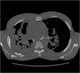

Progressive massive fibrosis

Progressive massive fibrosis (PMF), characterized by the development of large conglomerate masses of dense fibrosis (usually in the upper lung zones), can complicate silicosis and coal worker's pneumoconiosis. Conglomerate masses may also occur in other pneumoconioses, such as talcosis, berylliosis (CBD), kaolin pneumoconiosis, and pneumoconiosis from carbon compounds, such as carbon black, graphite, and oil shale. [Source: Wikipedia ]